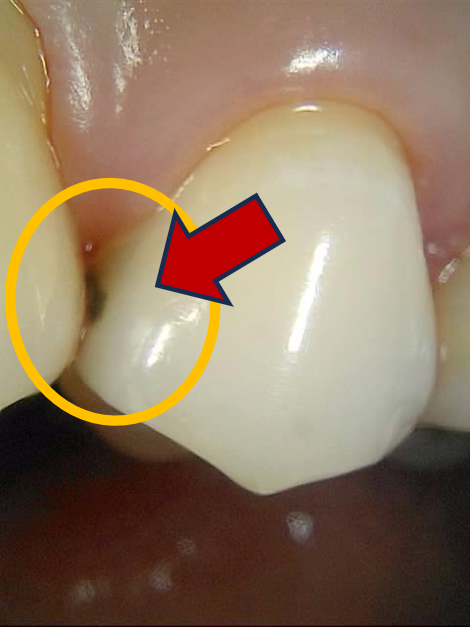

진단 : 치아 사이 검은 점 - 인접면 충치!

치아 사이에서 검은 점이 보인다. 여기서 살짝 긴장.

충치가 맞는지, 혹시 남은 치석은 아닌지 꼼꼼히 봤는데.. 역시나, 인접면 충치다.

인접면 충치 사진

하지만 이렇게 치아 사이를 넘어, 옆으로까지 퍼져서 눈으로 보일 정도가 되면..

추가적인 검사 없이도, 치료가 필요한 충치로 보는 것이 맞다. (이유는 아래에서..)

처음에 검은 점이 발견된 부위도 확인. 깔끔하게 레진으로 교체됐다.

인접면 우식 치료 전후사진, 인접면 레진

그러다가 점점 깊어지고 넓어지면, 아래 사진처럼 눈에 보이게 된다.

눈에 보이는 인접면 우식

인접면 충치가 이렇게 눈으로 보이는 상황이라는 건,

우연히 집에서 바퀴벌레 한 마리가 눈에 띈 것과 같다.

집에 숨어지내던 수 많은 바퀴벌레가 흘러넘쳐 내 눈에까지 보이게 된 것처럼,

저 깊은 곳에서 천천히 커지던 인접면 우식이 커지면서 눈에 보이게 된 것이다.